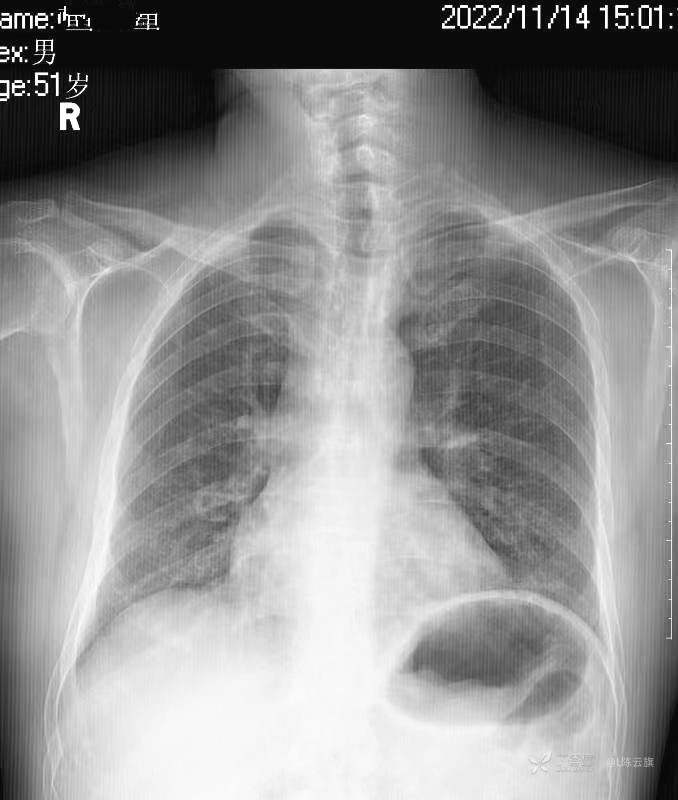

华夏览雄 达人已点赞1、患者男,51岁,精神病长期住院患者,主要病史只有时不时觉得腹部不适,其他不详。系列胸片为定期胸部检查。

3、根据系列复查胸、腹部平片的不同表现,你能否总结出什么征象和经验呢?